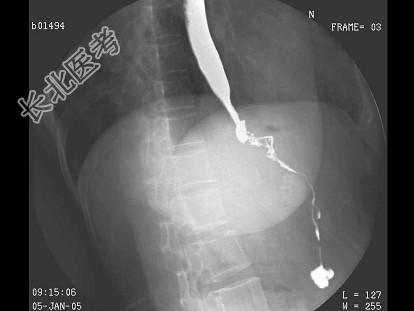

- 单项选择题女,53岁, 进行性吞咽困难伴呕吐,吐黏液半月, 结合图像,最可能的诊断为 ( )

A、食管癌

B、贲门癌

C、食管静脉曲张

D、贲门失弛缓

E、胃底癌